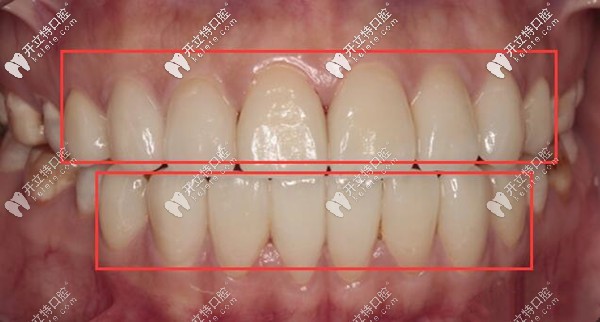

重度氟斑牙做瓷貼面修復(fù)后效果▼

重度氟斑牙做瓷貼面修復(fù)后效果

我在合肥壹加壹口腔,全口上下總共做了16顆瓷貼面,從咬模、磨牙,到粘上貼面,前后共用了7天的時(shí)間,去醫(yī)院了兩次;就成功的修復(fù)了我多年的重度氟斑牙。